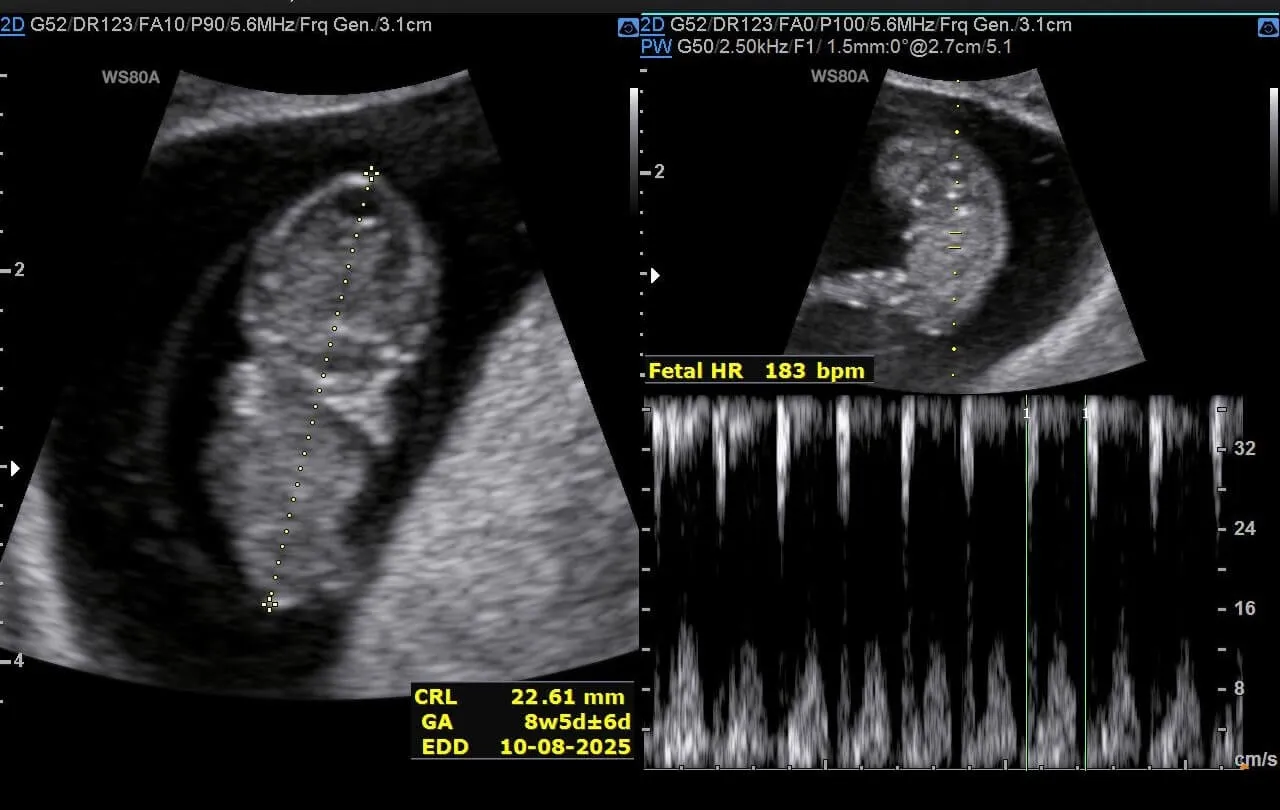

慢慢初具人形——

再到四肢、五官清晰可见,能在肚子里动来动去、打嗝、做体操。几个月来,我几乎无时无刻不在感叹和敬畏生命的神奇,碳基生命扳回一局!